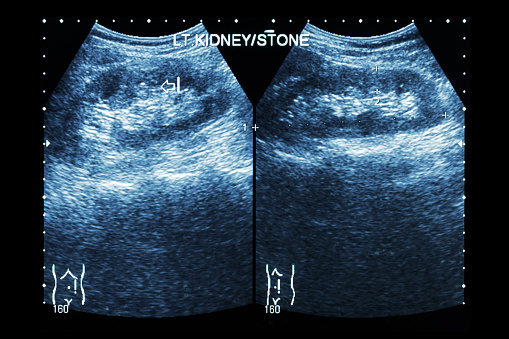

Dehydration can lead to kidney stones, kidney failure, and cardiac arrest

Dehydration can lead to kidney stones, kidney failure, and cardiac arrest. The risk of dehydration is much higher in the summertime, as the weather is hotter and people are outdoors and being active more often. While running low on liquid intake is usually associated with weakness and malaise, you should also know without proper hydration ...click here to read more